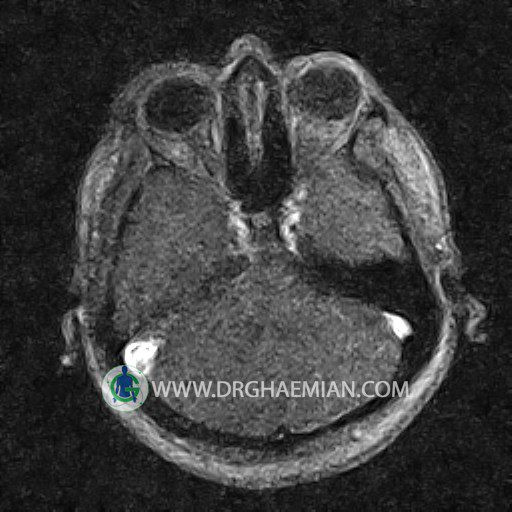

ام آر وی یک روش تصویربرداری دقیق و غیر تهاجمی است که برای معاینه ورید های بدن و ارزیابی سلامت رگ ها استفاده می شود. ورید ها خون را از اعضای بدن به قلب باز می گرداند تا دوباره اکسیژن و مواد مغذی به خون داده شود. ام آر وی جریان خون را ارزیابی و موارد غیرعادی مضر مانند لخته های خونی را شناسایی می کند. در این کیس ترومبوز دیواری مغز در سینوس عرضی راست و ترمبوز جزئی در سینوس عرضی چپ دیده می شود.

CRANIAL MRV

(With & Without contrast)

Technique: TOF ( time of flight ).

Images of the venous cranial vessels demonstrates a superior sagittal sinus of normal caliber with normal arrangement of draining superficial cerebral veins.

The great cerebral vein Galen inferior sagittal , straight sinus and left sigmoid sinus appear normal.

The right sigmoid sinus present a normal caliber.

The other evaluable deep cerebral veins , basal and labbe are normally developed and patent.

The other evaluable portions of the neurocranium show no abnormalities.

– Narrowing of left transverse sinus with filling defect & inthimal irregularity

suggestive for partial thrombosis

– Inthimal irregularity in anterior wall of right transverse sinus suggestive for mural thrombosis

are seen